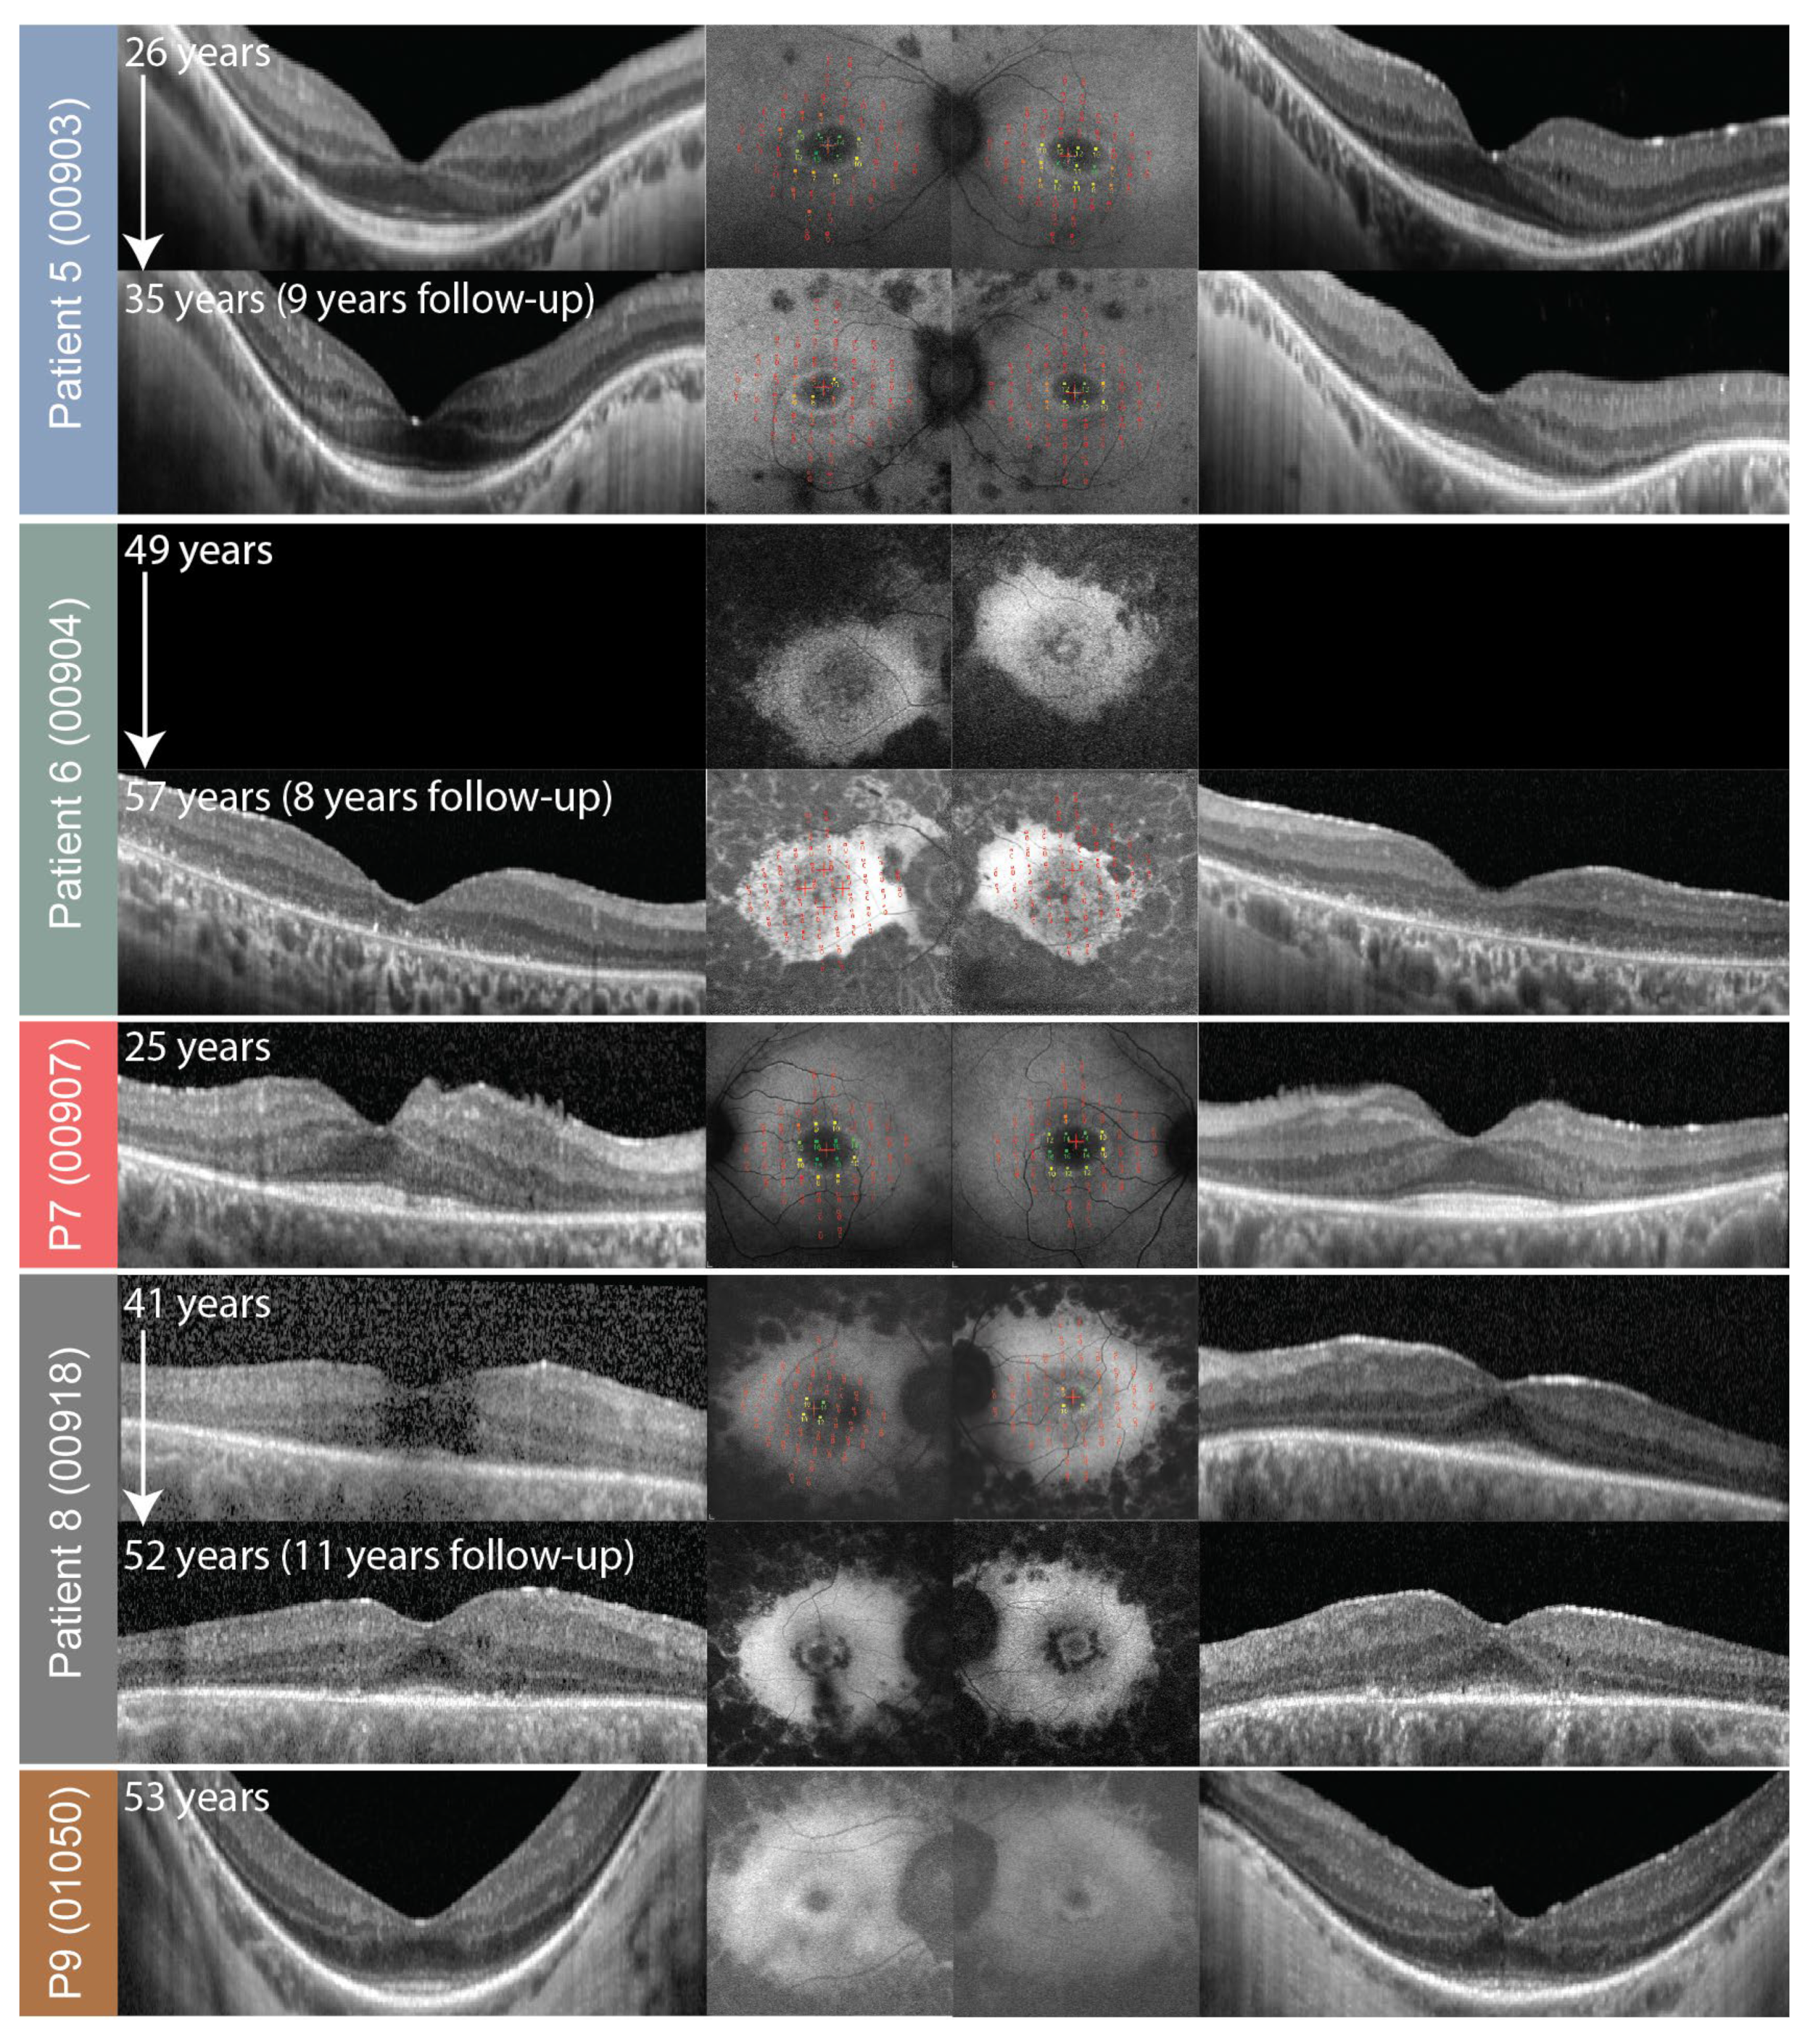

2.3. Fundus Autofluorescence and Optical Coherence Tomography

| 5 | 00903 | 0602 | p.(Cys870*) | p.(Cys870*) | Null |

| 6 | 00904 | 0603 | p.(Cys870*) | p.(Trp3955*) | Null |

| 7 | 00907 | 0606 | p.(Cys870*) | p.(Cys870*) | Null |

| 8” | 00918 | 0617 | p.(Cys870*) | p.(Trp3955*) | Null |

| 9” | 01050 | 0617 | p.(Cys870*) | p.(Trp3955*) | Null |

| 5 | M | 19 | 26 | 0.9 | 1 | 14 | 14 | 833; 40 | N/A | 2.6 | 2.6 | Ring | Ring |

| 35 | CF | 0.8 | N/A | N/A | N/A | N/A | 0.6 (36) | 1.4 (36) | Ring | Ring | |||

| 6 | F | 11 | 49 | CF | 0.4 | 0 | 0 | 322; 18 | 390; 19 | 0 (57) | 0 (57) | Atrophy | Patch |

| 64 | HM | HM | N/A | N/A | 256; 19 (60) | 221; 18 (60) | N/A | N/A | Atrophy | Atrophy | |||

| 7 | M | 23 | 25 | 1 | 1 | 13 | 13 | 426; 22 | 362. 22 | 2.9 (25) | N/A | Ring | Ring |

| 8” | M | 12 | 41 | 0.4 | 0.25 | 1 | 1 | 20; 5 | 29; 6 | 0.8 | 0.8 | Ring | Ring |

| 52 | 0.3 | 0.4 | N/A | N/A | N/A | N/A | N/A | N/A | Ring | Ring | |||

| 9” | F | N/A | 53 | 0.3 | 0.3 | N/A | N/A | N/A | N/A | N/A | N/A | Ring | Ring |